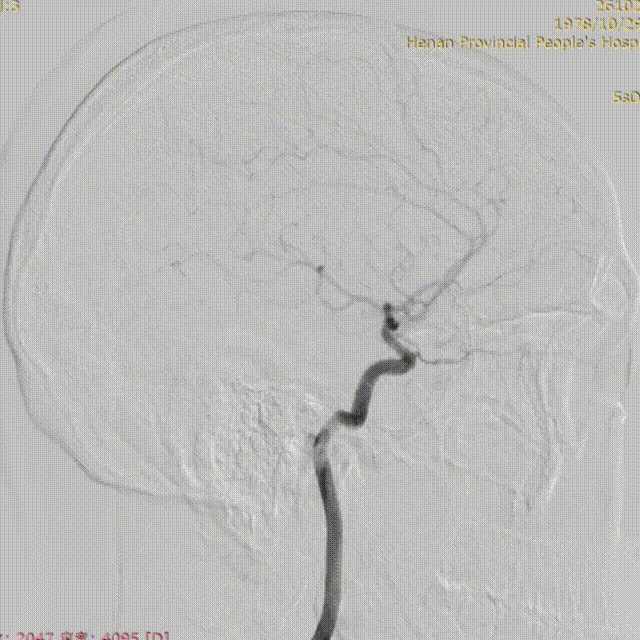

术后造影显示上矢状窦较前明显改善。

术前上矢状窦闭塞

术后上矢状窦再通